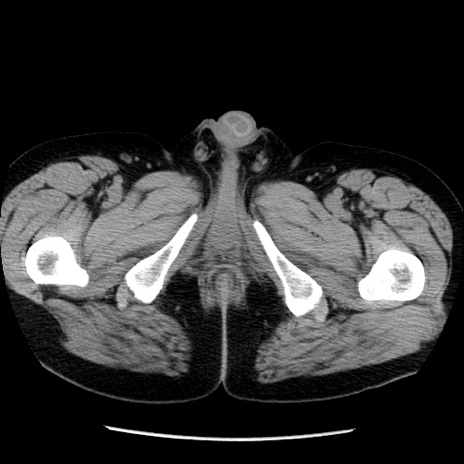

冠状断像

【症例】40歳代男性

【現病歴】2日前から胃痛あり。徐々に周期的な激痛に変化した。本日になっても激痛があるため受診。

【身体所見】意識清明、BT 38-39℃台あり、腹部:膨満、やや硬、右下腹部に圧痛あり。

【データ】WBC 8500、CRP 23.26